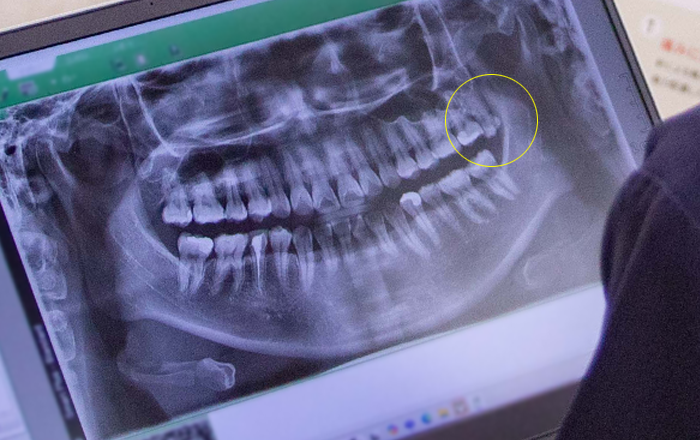

親知らずは、奥歯の中で最も後方に位置する永久歯で、前歯から8番目の歯です。上下左右で最大4本ありますが、生える本数には個人差があり、全く生えないケースも珍しくありません。

「智歯(ちし)」や「第三大臼歯(だいさんだいきゅうし)」とも呼ばれ、10代後半から20代前半にかけて生えてくることが一般的です。昔は、この歯が生える頃には親と離れて暮らすことが多かったため、「親知らず」と呼ばれるようになったと言われています。